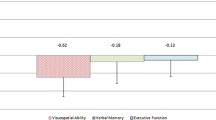

Compared to HCs, SCA3 patients showed cognitive domain impairments in information processing speed, verbal memory, executive function, and visuospatial perception. Between CI and CP subgroups, the CI subgroup was older and had lower education, as well as higher severity scores. VBM and ROI analyses revealed volume loss in cerebellar bilateral lobule VI, right lobule Crus I, and right lobule IV of the CI subgroup, and all these cerebellar lobules were associated with the above cognitive domain impairments.

Compared to the HCs, the SCA3 patients had lower MMSE and MoCA scores and had higher HARS scores; there were no differences for HDRS values between SCA3 patients and HCs. SCA3 patients showed lower scores in the respective tests of the modified MACFIMS of JLO (P < 0.05), COWAT (P < 0.0001), SDMT (P < 0.0001) and/or PASAT (both P < 0.0001), and CVLT-II (note that excepting the item score for free recall insert, the P values for item scores were all < 0.05) (Fig. 1A). There was no difference in BVMT-R scores between SCA3 patients and HCs. Raw neuropsychological tests scores for single items are shown in Table S4.

In terms of the five cognitive domains, information processing speed was the most common impaired domain, with 45.9% of SCA3 patients showing decreased PASAT and/or SDMT scores. The ranked order for impairment in the other cognitive domains is as follows: 27.8% of patients had verbal memory impairment showing decreased CVLT-II TL and/or CVLT-II DR scores, 13.2% had visual memory impairment showing decreased BVMT-R TL and/or BVMT-R DR scores, 11.2% had executive function impairment showing decreased COWAT scores, and 6.4% of patients had visuospatial perception impairment showing decreased JLO scores (Fig. 1B).

The most frequently impaired cognitive domain detected for the SCA3 patients of our cohort was information processing speed, followed by verbal memory, executive function, and visuospatial perception. SCA3 patients defined as cognitively impaired (CI) had longer disease duration, a lower level of education, and more severe motor function impairment compared to those defined as cognitively preserved (CP). Our MRI data enabled VBM and ROI analyses, which revealed that volume loss in segmented cerebellar lobules (bilateral lobule VI, right lobule Crus I, and right lobule IV, and especially left lobule VI) contributed to cognitive impairments in SCA3.